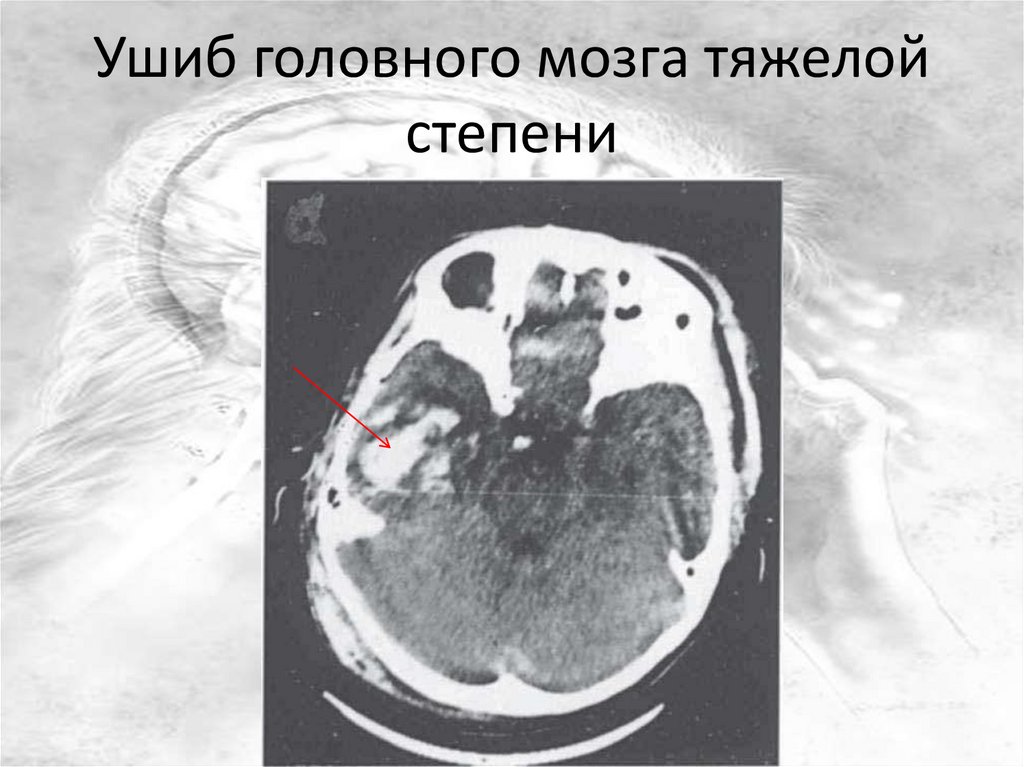

Ушиб головного мозга тяжелой

степени

Клиническая картина ушиба

головного мозга

• Утрата сознания от нескольких часов до

нескольких суток

• Ретроградная амнезия (потеря памяти о

событиях, предшествовавших началу

заболевания)

• Многократная рвота

• Выраженная общемозговая симптоматика

• Очаговая симптоматика: параличи, парезы,

нарушение речи, глотания, неравномерная величина

зрачков, судорожные припадки, нистагм, т.е.

выпадение функций мозга в соответствии с участком

повреждения